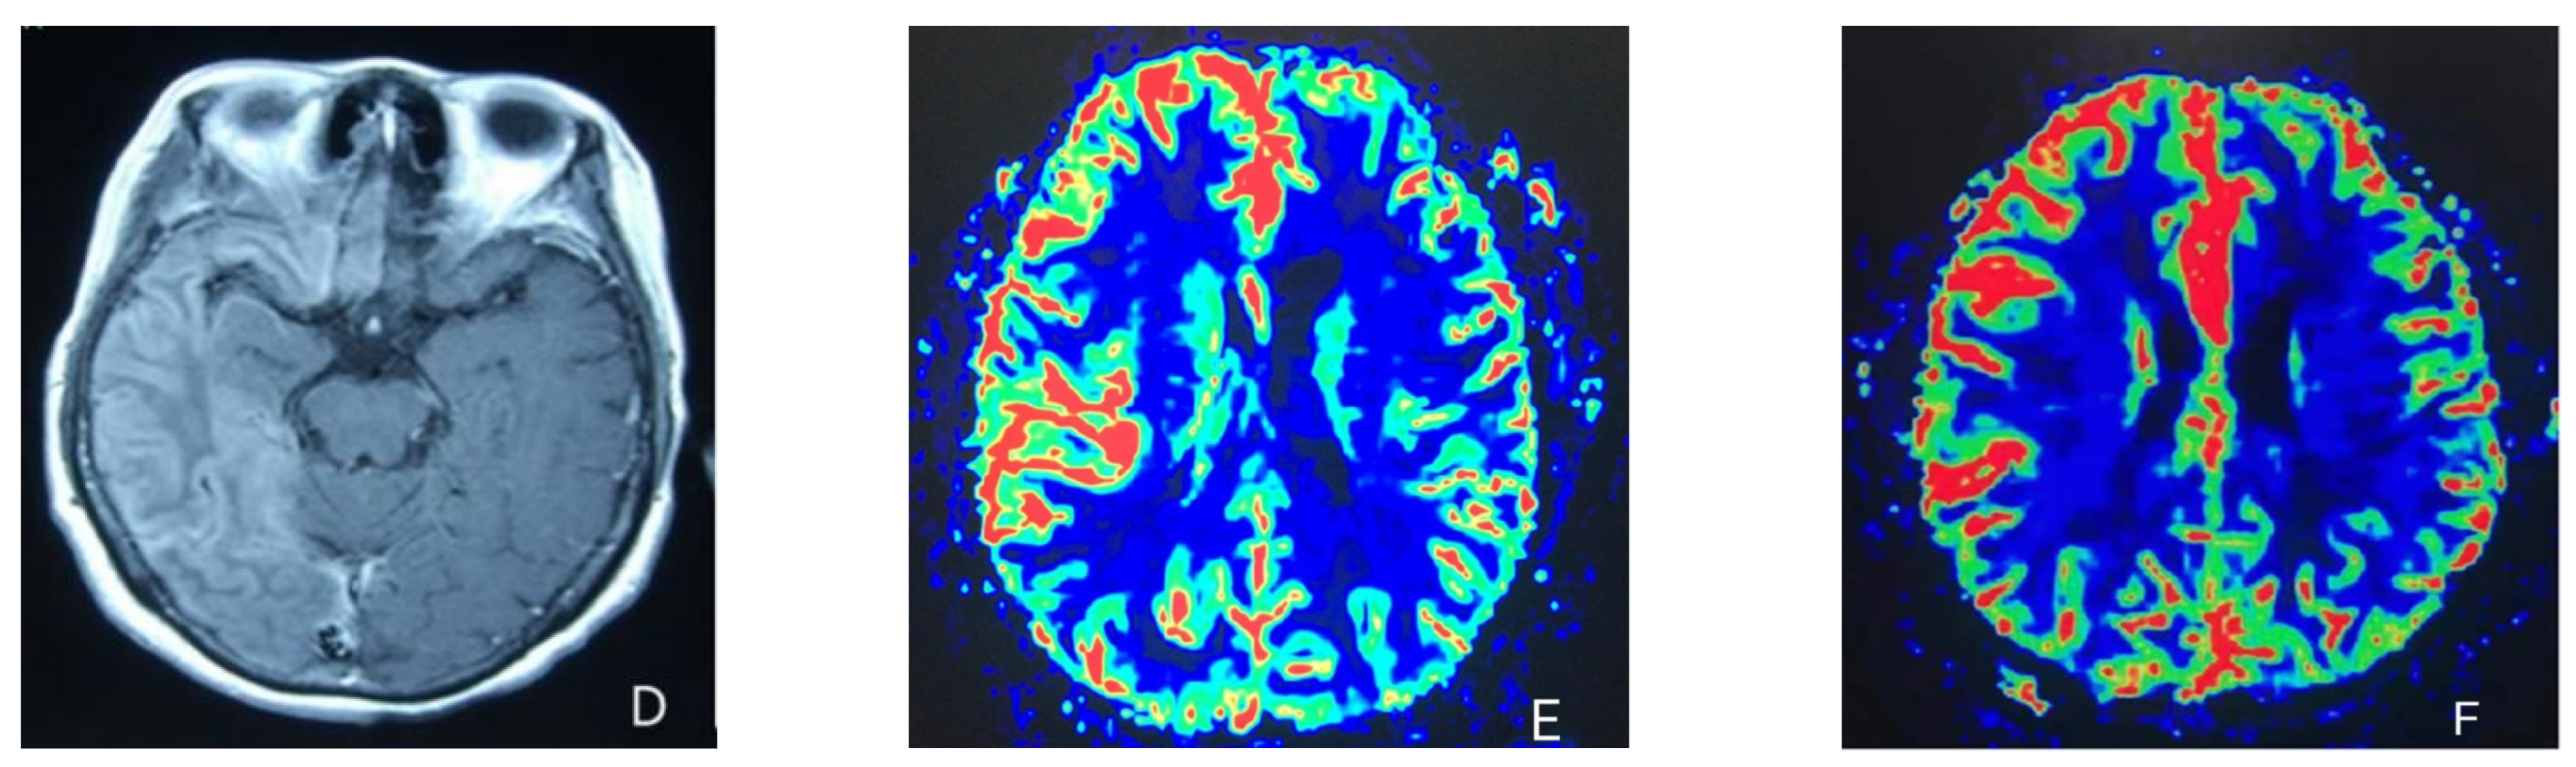

At the age of 51, she had a migraine attack with weakness in the left limb. The headache became increasingly serious, so she was admitted to a hospital six days after the attack. Upon admission, she had severe headaches and left limb weakness, and the neurological examination revealed left hemiparalysis with muscle strength at 3/5 by manual muscles testing (MMT). A brain MRI (magnetic resonance imaging) on day two of admission revealed cortical swelling in the right cerebral hemisphere (Figure 1A), and on the day three of admission, the magnetic resonance angiography (MRA) showed a slight decrease in the branches of the left middle cerebral artery (MCA). The main trunk of the left posterior cerebral artery (PCA) was slender contralateral, and its branches were significantly reduced contralaterally (Figure 1B). Symptoms persisted. On day five of admission, the patient had a focal epileptic seizure, which was followed by two more seizures. Subsequently, the patient’s left limb weakness gradually worsened, the neurologic examination revealed left hemiparalysis with muscle strength at 0/5 by MMT, and she gradually developed unconsciousness to light coma. Brain CT scans during coma revealed swelling of the right cerebral cortex (Figure 1C). Contrast-enhanced brain MRI showed swelling and diffuse enhancements in the cortex of the right cerebral hemisphere (Figure 1D). Perfusion-weighted imaging (PWI) showed right hemisphere hyperfusion (Figure 1E). Based on her medical history and presentation at admission, a lumbar puncture was performed, and the cerebrospinal fluid pressure (CSF) was 204 mm H2O. The biochemical and cytologic examination of the CSF revealed normal chloride, glucose and cell counts and classifications, in addition to normal protein levels. The CSF tested negative for bacteria, viruses, fungi and autoimmune encephalitis. Whole-exome sequencing showed a missense mutation (c.2473G > A, p.Glu825Lys) in exon 18 of ATP1A2. Based on a series of tests, the patient was diagnosed with FHM2 caused by a pathogenic ATP1A2 mutation. During hospitalization, we dehydrated the patient, gave the patient paracetamol for symptomatic treatment and an intramuscular injection of phenobarbital to control seizures. On the 15th day after admission, consciousness and hemiplegia improved, and the headache was relieved; the patient was discharged after 22 days. She was back to normal, and at later follow-up, the patient’s brain MRI (Figure 2A), contrast-enhanced brain MRI (Figure 2B), PWI (Figure 2C) and computed tomography angiography (CTA) all returned to normal (Figure 2D). The time course diagram of the disease in our patient is presented in Figure 3.

Figure 2.

(A,B) Previously demonstrated the swelling of cerebral cortex has resolved; (C) hyperfusion in the right hemisphere has returned to normal. (D) Bilateral MCA and PCA were relatively symmetrical.